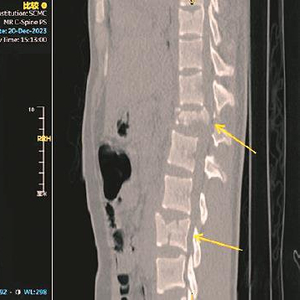

右下图:术后CT示椎体内固定位置稳定,骨折端对位、对线好

儿中心骨科王志刚主任团队接诊后,对孟迪的病情进行了详细的分析,为其制定了个性化的手术方案。由于患者系严重损伤所致的脊柱不稳定骨折伴神经损伤,已出现双下肢截瘫,病情危重,且存在神经压迫、损伤,为重建其脊柱稳定性,为了术后孩子能负重坐起,选择术中同时行减压手术,为神经脊髓功能的部分恢复创造环境,考虑采用目前行业内先进的导航技术及神经功能监测。相较于传统的手术方式,该技术能够在术中实现精确定位,协助医生在患者受伤的椎体精准置钉,从而减少内固定相关并发症,尽可能地避免椎体的疏松和不稳定,降低患儿二次损伤的几率,并大幅缩减手术时间。

最终,凭借着医生丰富的经验和精湛的技术,手术顺利完成。术后第二天,孟迪的双下肢便可自主完成上抬、屈膝等动作,且双足麻木感较此前明显好转,手术成效显著,为后续的康复治疗奠定了坚实基础。目前,孟迪正处于术后康复阶段,医院正继续予以营养神经、抗感染等对症处理,并将根据其恢复情况,及时调整治疗方案。